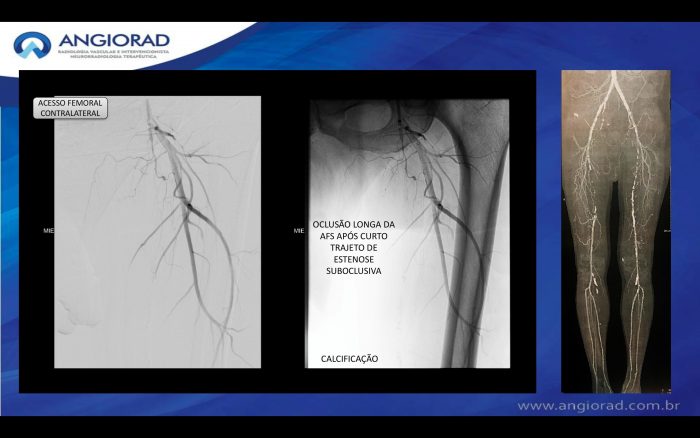

Paciente com história de claudicação dos membros inferiores para curtas distâncias, já submetido a angioplastia do membro inferior direito, retorna ao serviço com piora dos sintomas no lado esquerdo, sem lesão trófica (Rutherford 3)